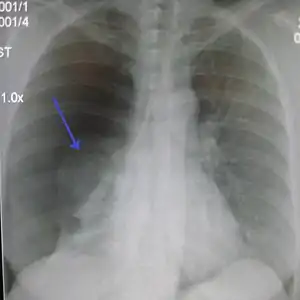

| پنوموتوراکس (p خوانده نمیشود) خود به خودی سمت راست. فلش لبه ریه جمعشدگی را نشان میدهد. | |

علایم اصلی شامل تنگی نفس، افزایش تعداد تنفس، درد سینه، سرفه، اضطراب و افزایش ضربان قلب است. هوای پرده جنب با فشار به ریه مانع تنفس میشود از اینرو هواجنبی فشارنده باید به سرعت درمان شود. تشخیص با سمع ریه و رادیوگرافی است. در معاینه کاهش یا عدم سمع صداهای تنفسی در سمت درگیر و هیپررزونانس در هنگام دق در سمت درگیر، انحراف تراشه به سمت درگیر نشده داریم. در عکس قفسه سینه ممکن است انحراف تراشه به سمت غیر درگیر و پس کشیدگی ریه (فضای کدر که نشاندهنده جمع شدن ریه است) از پلور پاریتال را ببینیم.